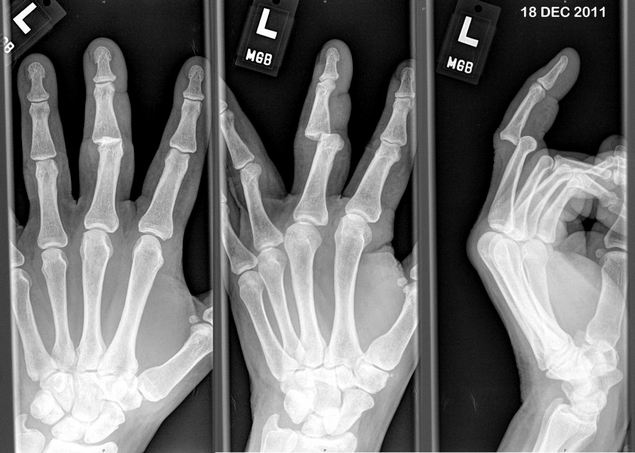

Первичный диагноз выставляется на основании внешнего осмотра, жалоб пациентов, данных анамнеза, результатов ряда функциональных тестов. Для его подтверждения проводятся рентгенография, МРТ, КТ, артроскопия. При подозрении на инфекционное происхождение патологии биологический образец высевается в питательные среды для установления вида бактерий, их резистентности к антибиотикам.